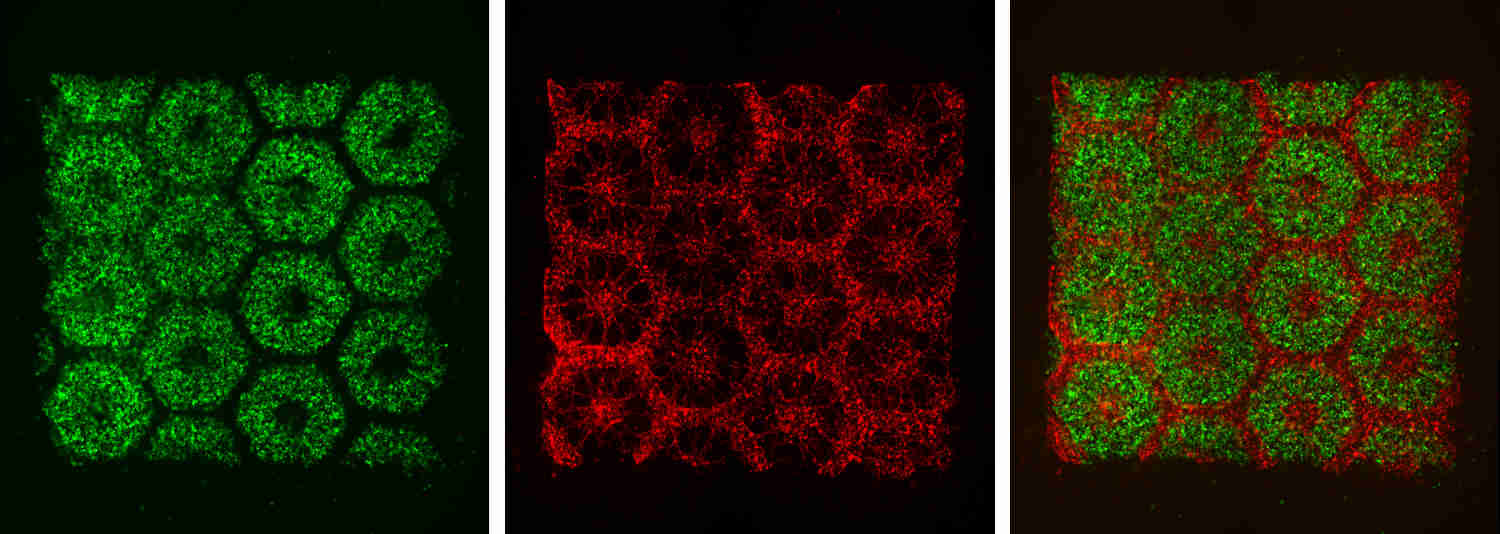

La imagen muestra células IPS (izq.), endoteliales y mesenquimales (centro) y la combinación resultante (dcha). Fuente: UC San Diego.

Para ello, el equipo emplea una nueva técnica de bioimpresión desarrollada en su laboratorio, que permite producir rápidamente microestructuras complejas en 3D que imitan con máxima precisión las características de los tejidos biológicos. La impresión se realiza en dos fases. En primer lugar se imprime un patrón con forma de panal, con hexágonos de 900 micrómetros, introduciendo en cada uno células hepáticas derivadas de células madre pluripotentes inducidas, normalmente abreviadas como IPS (por las siglas en inglés de Induced Pluripotent Stem), células procedentes de cualquier parte del cuerpo que son capaces de “reprogramarse” como células madre.

A continuación, en una segunda fase se imprimen las células mesenquimales, que sirven de soporte entre los hexágonos, y las endoteliales para reproducir los vasos sanguíneos. En total la estructura completa es un cuadrado de 3x3 milímetros y 200 micrómetros de grosor, que tarda escasos segundos en imprimirse. Esta es otra gran mejora frente a métodos de impresión anteriores, que normalmente requieren horas.